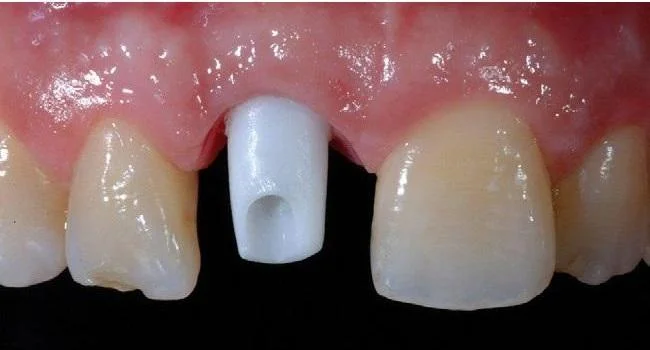

Step 3: Scanning periodontal tissue, occlusion, and implant position to fabricate customized abutment and crown.

Scanning is performed after the implant has integrated and stabilized, usually 2 months after implant placement.

Unlike traditional implant methods that use manual impressions, personalized implants use scanning technology for impression taking. This technology not only accurately records the implant position but also precisely captures the morphology and structure of periodontal tissues and the patient’s occlusion to transfer into virtual design software.

Step 4: Placement of the customized abutment and fixation of the ceramic crown.

After scanning, the data is sent to the design center for simulation. The customized abutment is manufactured there and then placed intraorally. The abutment is designed to fit precisely with the periodontal tissue structure.